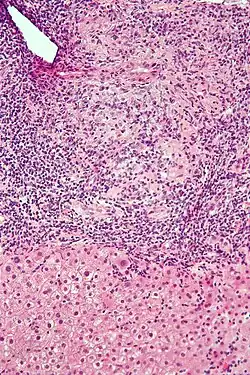

Low-magnification micrograph of PBC, H&E stain -

On microscopic examination of liver biopsy specimens, PBC is characterized by chronic, nonsuppurative inflammation, which surrounds and destroys interlobular and septal bile ducts. These histopathologic findings in primary biliary cholangitis include:[32]

- Inflammation of the bile ducts, characterized by intraepithelial lymphocytes

- Periductal epithelioid granulomas.

- Proliferation of bile ductules

- Fibrosis (scarring)

The Ludwig and Scheuer scoring systems have historically been used to stratify four stages of PBC, with stage 4 indicating the presence of cirrhosis. In the new system of Nakanuma, the stage of disease is based on fibrosis, bile duct loss, and features of cholestasis, i.e. deposition of orcein-positive granules, whereas the grade of necroinflammatory activity is based on cholangitis and interface hepatitis. The accumulation of orcein-positive granules occurs evenly across the PBC liver, which means that staging using the Nakanuma system is more reliable regarding sampling variability.